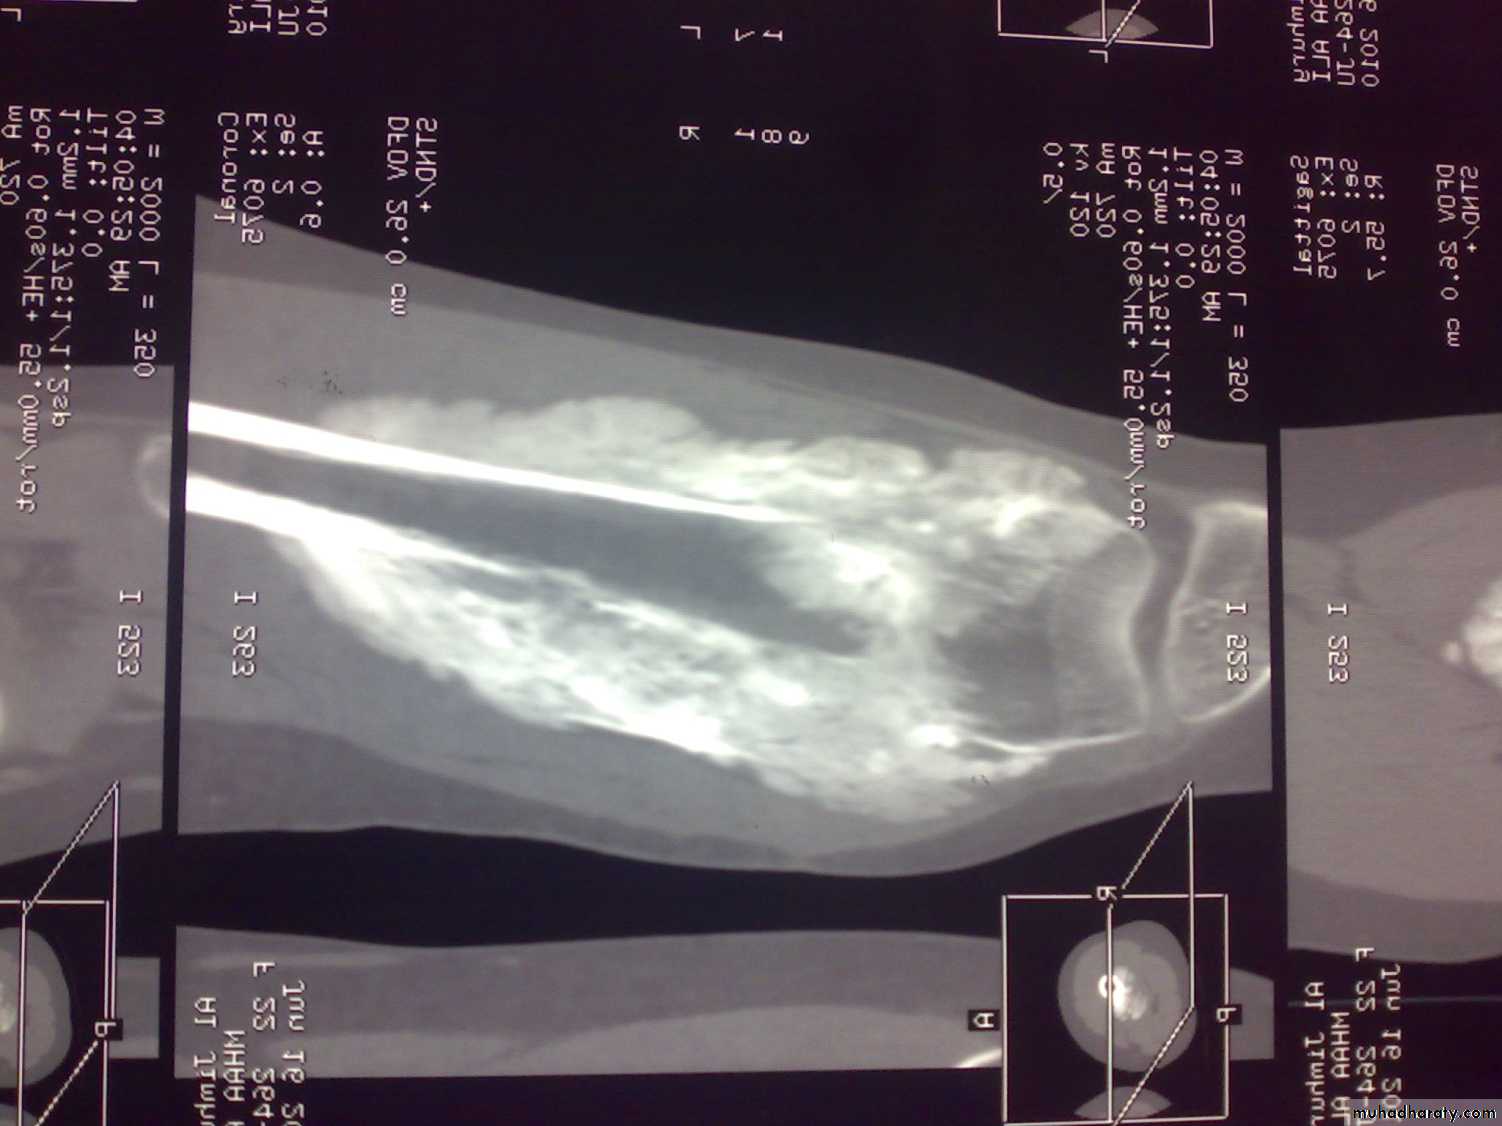

Reading of radiofrequency emissions from atoms and molecules of tissues exposed to static magnetic field.

Indications:

Bone tumors; size and spread.

Spinal disorders; eg disc prolapse.

Cartilage and ligament. Eg meniscus and anterior cruciate ligament injuries.

MRI of osteosarcoma of femur

MRIFree of ionizing radiation.

Limitations:

Metallic foreign bodies and implants.

Overweight.

Fear of closed spaces.

Irritable patients and children.